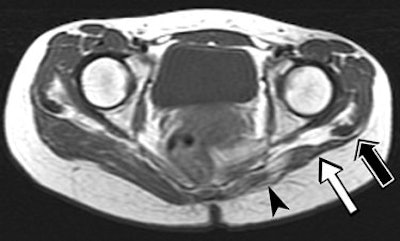

| A 23-year-old woman suffering from bilateral gluteal contracture that is more severe on left side. Patient related history of repeated injections in both buttocks since adolescence. Spin-echo T1-weighted axial image (TR/TE, 566/16) shows atrophic and medial retraction of left gluteus maximus muscle (arrowhead), thickening and retraction of fibrotic cord and distal tendon (white arrow), and displacement of iliotibial tract (black arrow). |

Among the 21 patients, 17 had a contracture of the bilateral gluteus maximus muscles while four had lesions on the right buttock only. All buttocks showed primary features of muscle atrophy and intramuscular fibrotic cord contiguous to the iliotibial track, which manifested as low signal intensity.

"Retraction of the thickened tendon and fibrotic cord accounted for the secondary MRI features," they wrote, such as medial retraction of the affected muscle and a depressed groove at the muscle tendon junction. "The muscle atrophy affected most commonly the upper third of the gluteus maximus, which is related to the injection technique."

The group concluded that the severity of the clinical abnormality can be judged by the presence of thickening and retraction of the fibrotic cord on MRI. In more advanced cases, a depressed groove will appear at the muscle-tendon junction, they added.